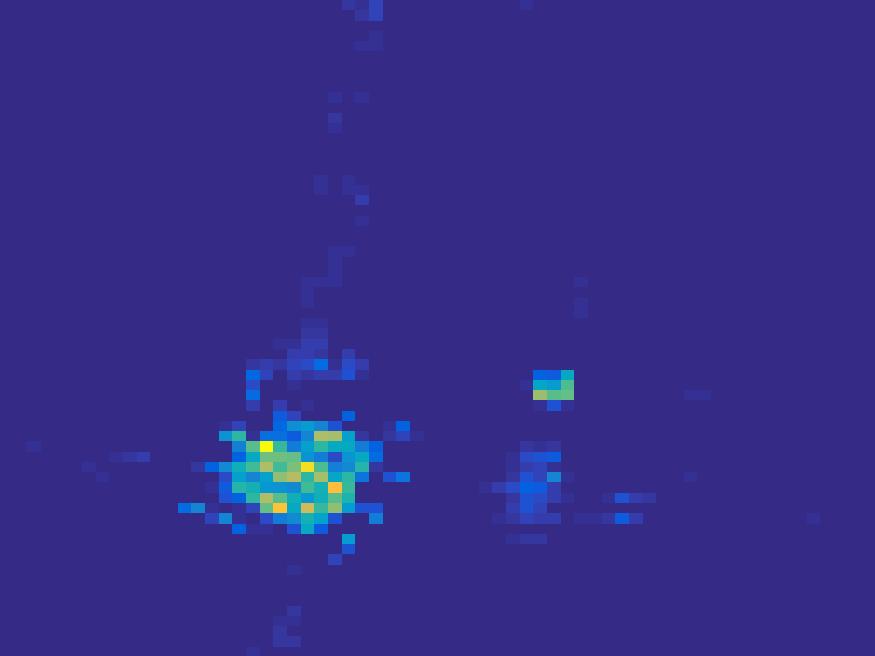

In order to test the performance of the proposed method in a more realistic scenario, we perform a Monte Carlo simulation for dynamic SPECT imaging. First, we created a phantom image consisting of three circles as region of interests, shown in Figure 13. The TAC over a time period of 90 time steps of the outer and the two inner circles were displayed in 13(b).

For each single frame, the photon counts is a probability proportional to the concentration in every region. The events are detected by a virtual double heads gamma camera rotating around the patient by degrees per time step, which consists of detector bins. Every simulated decay event is projected and counted by the corresponding detector bin.

We set the number of events counted by the detector as and ) times the average concentration in one pixel of two different tests. The signogram images the count in each bin of two settings are shown in Figure 14.

Based on the sinogram data, we compare the proposed method with the alternating EM algorithm. The results for both test cases are shown in Figure 15. We can see that for the case of a low count number, the proposed method is able to reconstruct the regions properly. Within a number of iterations, the algorithm presents a reasonable reconstruction of the region of interest and the corresponding regional tracer concentration curves.